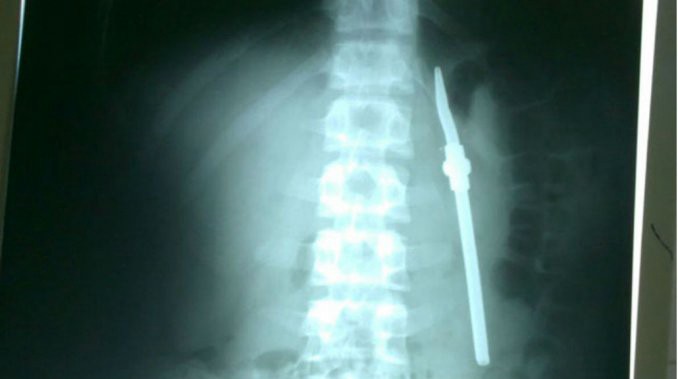

Cuando los guardias fueron informados, el joven fue trasladado de urgencia a la unidad de atención médica de la propia cárcel y de ahí al Hospital San Martín donde se le realizó una placa que detectó el elemento que había ingerido. La cirugía de extracción se practicó en horas de la tarde y se le extrajo la bombilla. El parte médico indica que su evolución es favorable y que podría volver a su lugar de detención en dos o tres días.